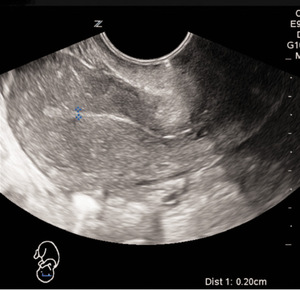

Lekarz dyżurny izby przyjęć wykonał doraźne badanie ultrasonograficzne sondą przezpochwową. W badaniu nie uwidoczniono ciąży wewnątrzmacicznej, stwierdzono cienkie, linijne endometrium (ryc. 1).